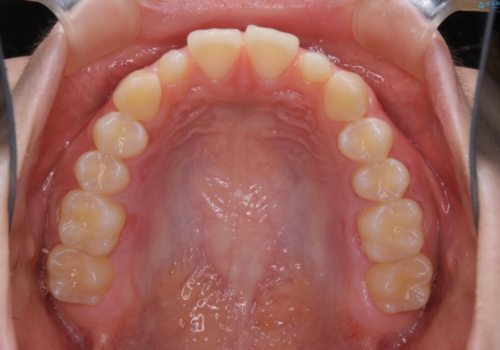

前歯や小臼歯では、生えてくる歯が小さく審美的に影響が出る場合があります。このような歯を矮小歯(わいしょうし)と言います。

今回のケースでは、歯が小さいだけでなく傾斜もしていたため補綴治療時に歯を削ることで神経の症状が出る可能性がありました。そのため、事前に部分矯正を行い歯軸の改善を行っておくことで、歯髄を温存することができました。

奥歯の噛み合わせに問題がなく、矯正で必要となる歯牙の移動量が軽微である場合に部分矯正が適用になる場合があります。

変える必要のない部分には手を出さず、必要な部分に最小限の処置を施すことで費用や期間の削減をすることが可能となります。